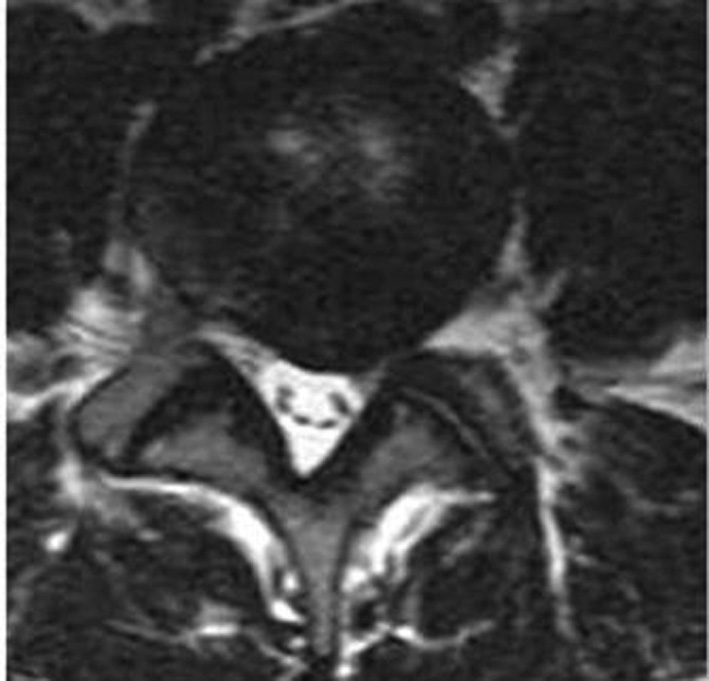

Six mois plus tard, le tableau persiste et une aggravation est perceptible depuis quatre mois. Une IRM est réalisée (clichés ci-dessous ; coupe axiale en L5-S1).

Quelle interprétation faites-vous de l’IRM ? Quel traitement proposez-vous ?